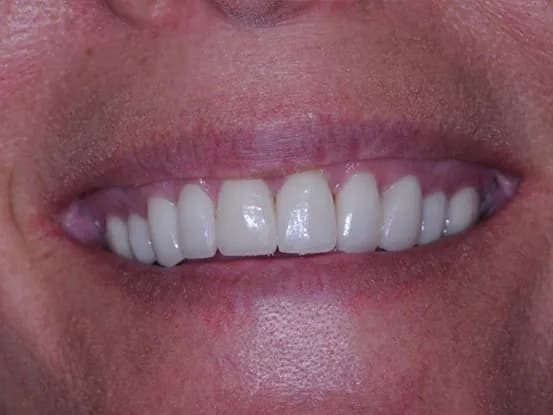

Case 7

38 year old female with extensive cervical caries from a high sugar diet and poor oral hygiene. 12 units of porcelain crowns and composite fillings to restore form and function followed by frequent recall visits